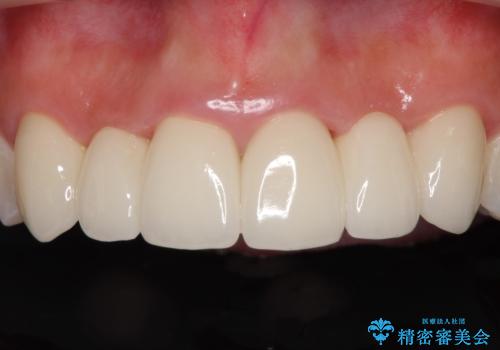

矯正治療により下顎前歯を整列させたため、上顎前歯のセラミックブリッジを補綴することで口元を少し下げることができました。

ヒトの目線がいつも口元に向けられているように感じることがなくなり、患者様には大変満足していただきました。